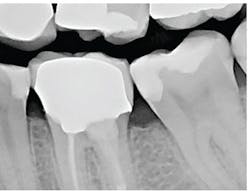

The patient was anesthetized with 1.7 ml of 4% articaine with epinephrine 1:100,000. The entire procedure was performed using the "Hard and Soft Tissue" setting. The gingiva was flapped to expose bone using the 0.25 mm spot size with 1% mist and cutting speed between 20% and 50% (figures 9-10). Only 0.5 mm of tooth structure was coronal to the alveolar bone. The osseous tissue was removed to establish biologic width and expose tooth structure coronal to bone for a proper restoration (figure 11). Proper positive bony architecture was maintained. The 0.75 mm spot size was used with 100% mist and cutting speed between 30% and 60%. A temporary restoration was placed, followed by one suture (figure 12). The total procedure time was 50 minutes. The patient was reevaluated after seven days (figure 13), and the final crown was placed (figure 14).

With traditional instruments, this procedure is typically completed with a scalpel and high-speed handpiece with burs. A larger flap is required to improve visibility and instrumentation. However, with Solea's precision and small spot-size options, a much smaller flap was needed. There was less bleeding, resulting in a cleaner surgical site and faster postoperative healing. As the radiograph and photos show, excellent conditions for the final restoration were established. The final crown demonstrated sound margins and evidence of proper biologic width. As the five-day follow-up photo shows, the healing time was fast, and tissues appear healthy.

Figure 13: Seven-day follow-upCrown lengthening

Figure 14: Crown inserted